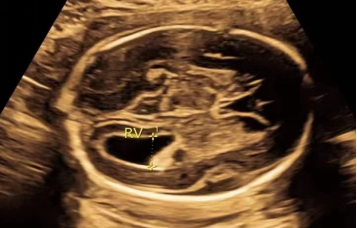

1.什么是侧脑室增宽?

胎儿侧脑室增宽是指侧脑室房部径线≥10mm。2018年美国母胎医学会指南指出,建议将侧脑室增宽分为轻度、中度、重度三种情况:轻度10mm-12mm,中度13-15mm,重度>15mm。